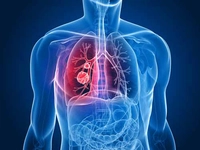

Temiz Akciğer Tomografisi Ne Anlama Geliyor?Günümüzde tıpta tanı ve tedavi süreçlerinde önemli bir yer tutan görüntüleme yöntemlerinden biri olan akciğer tomografisi, hastalıkların teşhisinde kritik bir rol oynamaktadır. "Temiz akciğer tomografisi" ifadesi, genellikle akciğerlerde herhangi bir anormal bulguya rastlanmadığı anlamına gelir. Bu bağlamda, temiz bir akciğer tomografisi sonucu, hastanın akciğer sağlığının iyi olduğunu gösterir. Akciğer Tomografisi Nedir?Akciğer tomografisi, yüksek çözünürlüklü görüntüler elde etmek için X-ray teknolojisini kullanan bir görüntüleme yöntemidir. Bu yöntem, akciğerlerin iç yapısının detaylı bir şekilde incelenmesine olanak tanır. Tomografi, akciğerlerdeki lezyonlar, tümörler, enfeksiyonlar ve diğer patolojilerin tespit edilmesinde son derece etkili bir yöntemdir. Temiz Akciğer Tomografisi SonucuTemiz bir akciğer tomografisi sonucu, şu durumları ifade edebilir:

Bu sonuç, genellikle hastanın akciğer sağlığının iyi olduğunu ve herhangi bir ciddi patoloji olmadığını gösterir. Ancak, bu sonuçlar her zaman kesin bir tanı anlamına gelmez; doktorun klinik değerlendirmesi ve hastanın genel sağlık durumu da göz önünde bulundurulmalıdır. Temiz Akciğer Tomografisinin ÖnemiTemiz akciğer tomografisi sonucu, özellikle kronik akciğer hastalığı, kanser riski veya enfeksiyon öyküsü bulunan hastalar için büyük bir rahatlık kaynağıdır. Bu durum, hastaların tedavi süreçlerine olumlu yönde katkı sağlar ve gereksiz endişeleri azaltır. Ayrıca, temiz bir tomografi sonucu, sağlık profesyonellerine hastanın durumu hakkında daha fazla bilgi verir ve gelecekteki muayene ve tedavi planlamalarına yardımcı olur. SonuçTemiz akciğer tomografisi, akciğer sağlığının iyi olduğunu gösteren önemli bir bulgudur. Ancak, bu sonucun değerlendirilmesi için mutlaka bir sağlık profesyoneliyle görüşülmesi gerektiği unutulmamalıdır. Her durumda, kişinin genel sağlık durumu, belirtiler ve diğer tetkiklerin sonuçları birlikte ele alınmalıdır. Sağlıklı bir yaşam tarzı, düzenli kontroller ve zamanında yapılan tetkikler, akciğer sağlığının korunmasında önemli rol oynamaktadır. |